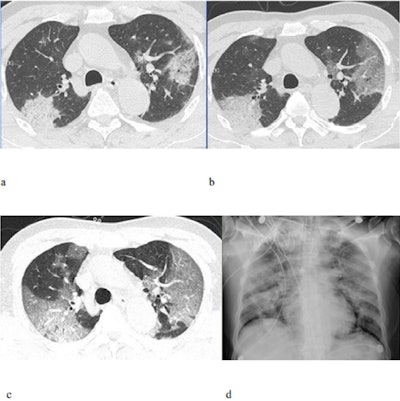

The group, led by Dr. Yuxin Shi, PhD, identified bilateral ground-glass opacities on the CT scans of almost 90% of the patients -- by far the most common imaging finding -- confirming reports from earlier studies.

To be specific, the ground-glass opacities were classified as pure in 77% of the cases, associated with interstitial and/or interlobular septal thickening in 75% of the cases, and associated with consolidation in 59% of the cases. In addition, the opacities involved the peripheral lungs in 86% of the patients and the posterior lungs in 80%. They also found that 80% of the patients' CT scans showed bronchograms and 55% had a consolidation lesion.

Overall, the most common CT findings for 2019-nCoV coincided with the most common findings for other viruses, including the 2009 swine flu virus (H1N1). The distinguishing characteristic for 2019-nCoV was that the imaging findings tended to appear simultaneously in the same patient, with predominant distribution in the posterior and peripheral part of the lungs.